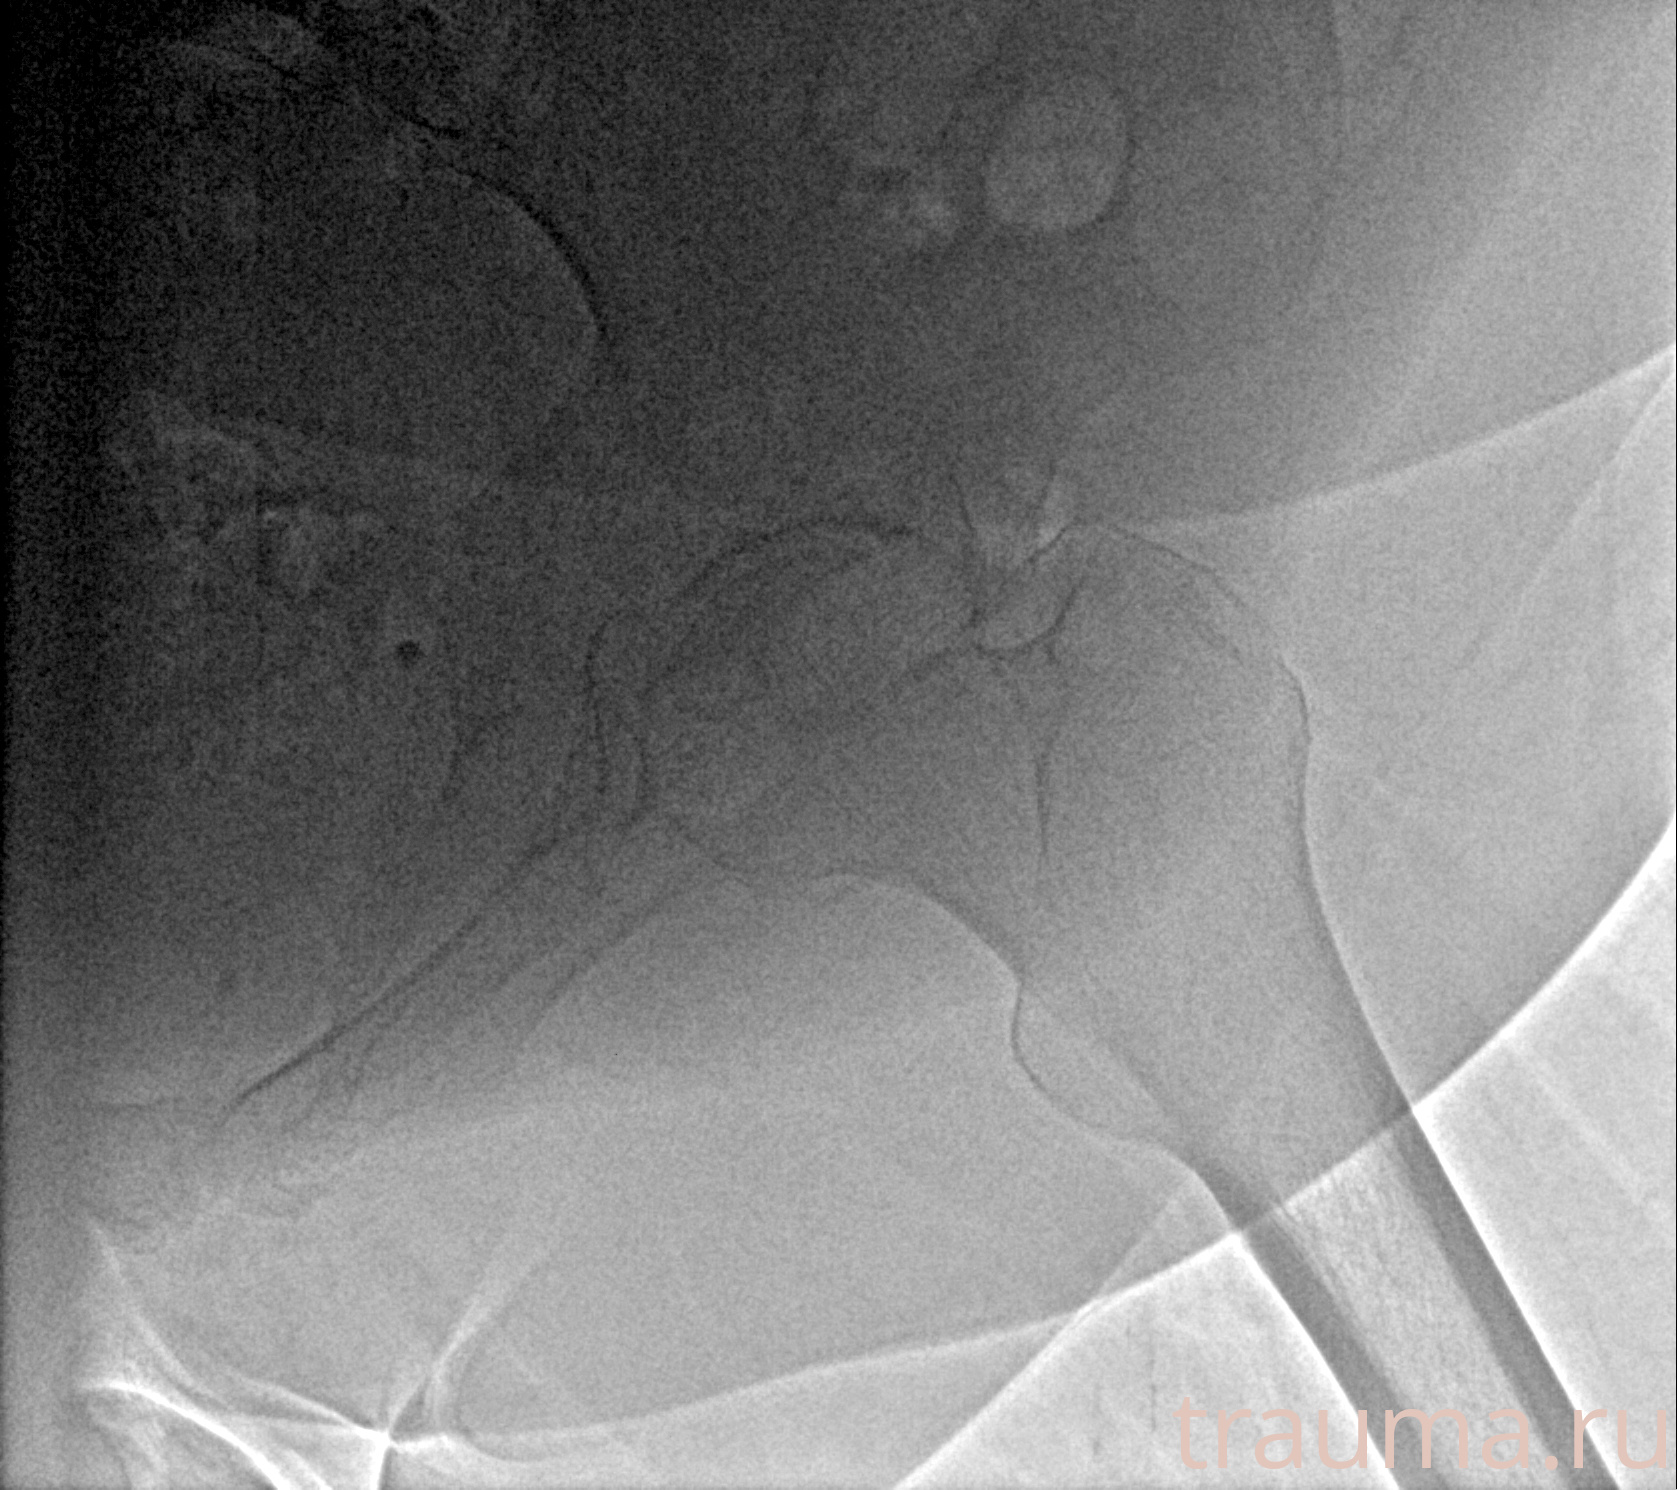

Рентгенограммы

Рентген на дому: по вашему адресу приезжает врач-рентгенолог, травматолог-ортопед с мобильным рентгеновским аппаратом, проводит диагностику травмы или заболевания, делает необходимые рентгенограммы, дает рекомендации по дальнейшему лечению. Получить качественные снимки в домашних условиях возможно благодаря уникальной методике, разработанной МосРентген Центром для института  Склифосовского